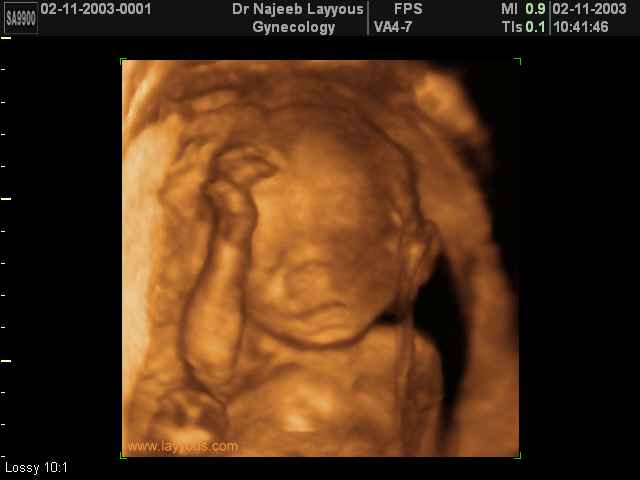

3D second trimestre échographie Photos de numérisation - deuxième partie de la grossesse | Dr N Layyous

3D second trimestre échographie Photos de numérisation - deuxième partie de la grossesse